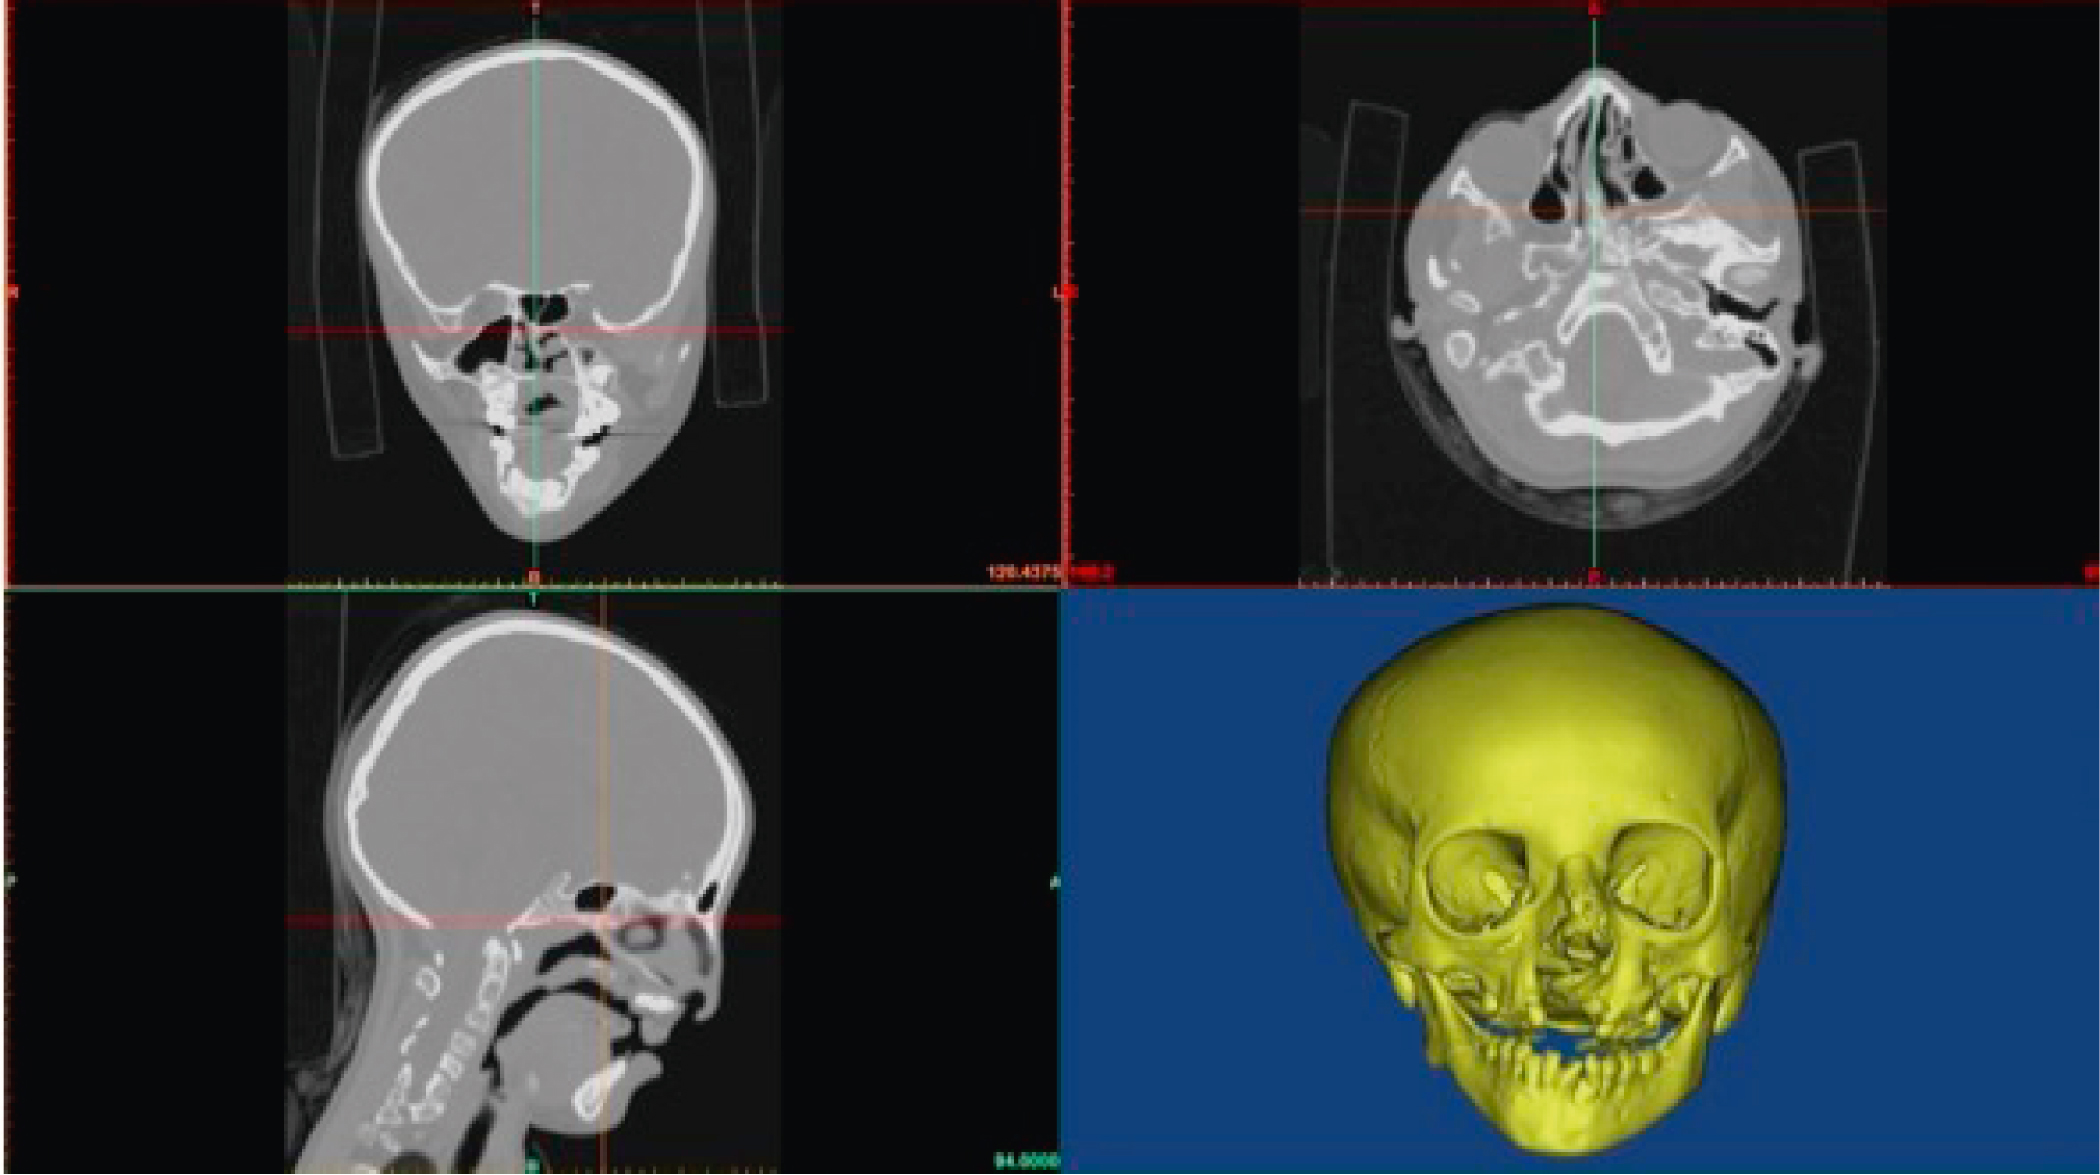

Contemporary CT scanners utilize multiple arrays of x-ray detectors and sophisticated helical-shaped radiation emission patterns, allowing for faster scans, more robust data collection, and undistorted image display in all anatomic orientations (axial, coronal, and sagittal) ( Fig. 7.2 ).